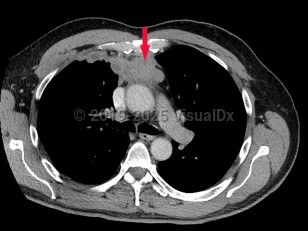

Thymoma

Rare tumor of the thymus, arising in the anterior mediastinum from thymic epithelial cells and lymphocytes. Mostly benign, but with a malignant and metastatic form. Onset is typically in the fifth and sixth decade; it rarely occurs in children. Associated disorders include myasthenia gravis (30%), pure red cell aplasia, hypogammaglobulinemia (Good syndrome), and other systemic diseases. Associated with autoimmune disease in approximately 40% of diagnosed adults. Signs and symptoms associated with tumor growth include neck mass, dyspnea, cough, chest pain, and muscle weakness.